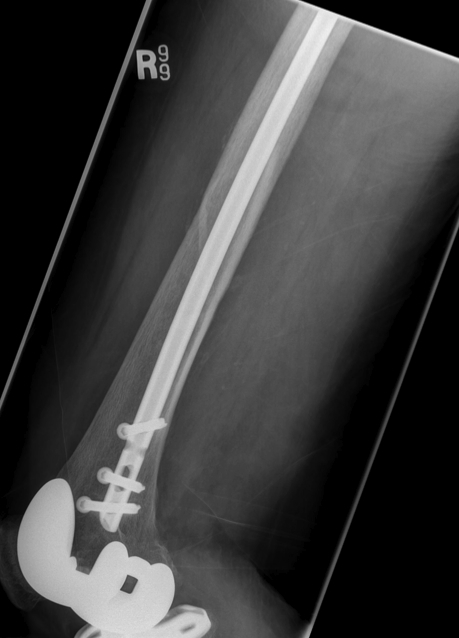

2.  Retrograde IM Nail

TKR Periprosthetic FractureTKR Periprosthetic Fracture 2TKR Periprosthetic Fracture Retrograde Nail 1TKR Periprosthetic Fracture Retrograde Nail 2

Issue

May be biomechanically superior

Have to open TKR to perform operation

- risk deep infection

Indications

Technically feasible

- CR knees contra-indicated

- must have sufficient sized hole in PS femoral component

- consult company as to suitablity

- small diameter nail

Technique

Minimum intercondylar distance of 12 mm

- AGC 18MM

- PFC = 20MM

- Genesis = 20MM

Usually remove polyethylene component

- replace after nail

- usually need new poly